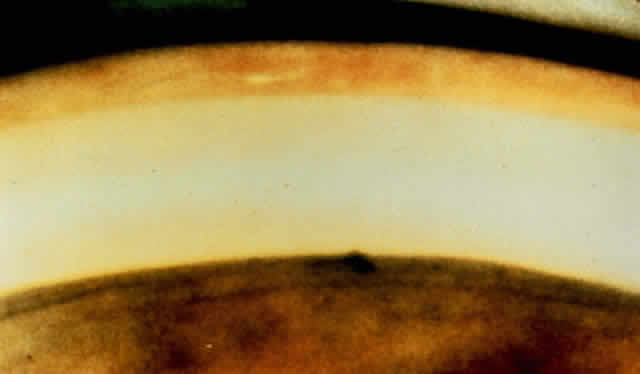

Signs On early examination, the cardinal sign of primary acute angle-closure glaucoma is present: a fixed mid-dilated pupil. There is profound reduction in central visual acuity. Photophobia and conjunctival hyperemia are striking external findings (Fig. 6). Intraocular pressure usually exceeds 40 mmHg and may be as high as 70 or 80 mmHg during the attack. On biomicroscopy, perilimbal hyperemia with a ciliary flush is accompanied by peripheral conjunctival and episcleral congestion. The peripheral iris bulges anteriorly and comes in close contact with the peripheral corneal endothelium for 360 degrees. Early microcystic epithelial corneal edema evolves to stromal edema. The anterior chamber appears shallow but formed centrally with cells, pigment and aqueous flare. Sustained high intraocular pressure affects the iris sphincter muscle, as well as its blood supply.33 Ischemia of sectors of the iris develop, probably due to compression of nutrient radial iris vessels causing infarction of the compromised iris and possibly also the ciliary body. This results in the release of debris and proteins, causing an aseptic anterior uveitis. If gonioscopy is obscured by corneal epithelial edema, application of topical 100% glycerol on the anesthetized cornea will often clear the edema sufficiently to permit adequate visualization of the peripheral anterior chamber and angle structures. During an attack, one sees only the cornea and iris meeting directly, with no evidence of the angle entrance or angle structures (Figs. 7 and 8). Indentation gonioscopy, introduced by Forbes,34 may be useful to differentiate between appositional and synechial closure of the angle. Central compression with a four mirror gonioscopy lens on the central cornea pushes the central aqueous to the peripheral anterior chamber. This maneuver pushes the peripheral iris posteriorly and opens an appositionally closed angle. If peripheral anterior synechiae are present, the angle will not be opened with indentation. The lower the initial pressure, the easier the examination. If the pressure is extremely high, indentation gonioscopy is extremely difficult, painful, and the cornea may be too edematous to allow visualization. If despite corneal dehydration with glycerol, edema of the affected eye precludes clear gonioscopy, examination of the angle structures of the fellow eye is often helpful. An extremely narrow closeable angle is usually present in the fellow eye giving strong evidence to the diagnosis of angle closure of the affected eye. Funduscopic examination is usually of little value because it is commonly precluded by corneal edema. When possible, early ophthalmoscopy shows pulsation of the retinal arterioles.